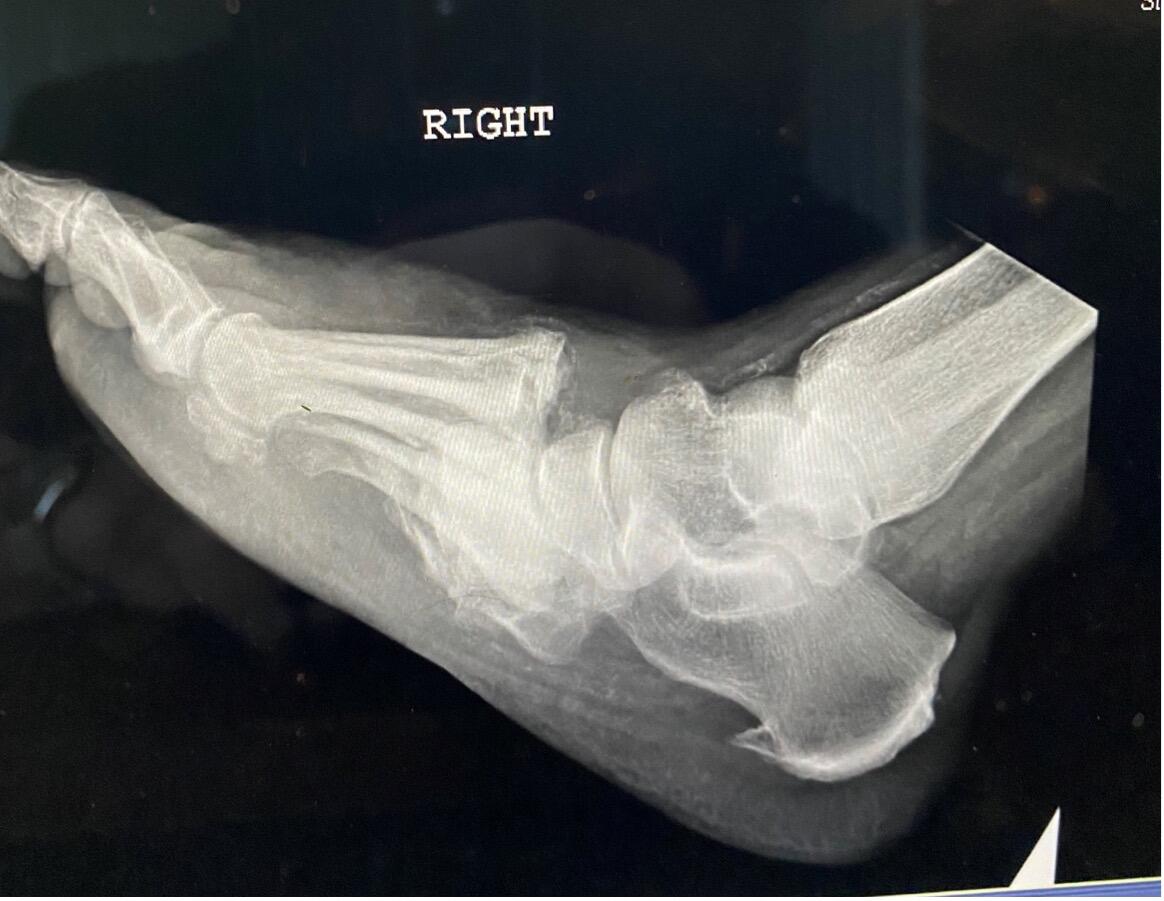

A Challenging Case Of Limb Preservation For A Patient With Neuropathic Pedal Dislocation

In the summer of 2020, an 82-year-old male presented to the emergency department to evaluate right foot pain and swelling over the past week. He saw his primary care physician earlier in the morning, who referred him for more emergent evaluation. He states he fell at home one week ago, injuring his right foot. This initially resulted in minimal pain, but over one week, the pain and swelling continued to worsen. He notes that he had no open wounds or active bleeding at the time of the initial injury. However, over that week, in addition to the escalating pain and swelling, he developed a bleeding ulcer on the dorsal aspect of the right foot. He could stand and ambulate, albeit with discomfort. He states that weight-bearing and ambulating for prolonged periods exacerbate his symptoms. He notes that the pain today is moderate and that he has not tried any therapy to relieve his pain besides rest, which only marginally helped. The worsening pain, swelling and bleeding prompted his visit to his primary physician.

Wound cultures revealed colonization by Pseudomonas spp. susceptible to ciprofloxacin. Laboratory examination was normal, and in fact, the ED physician initially had concerns for possible compartment syndrome. Examination revealed a foot that was cool to the touch, with non-blanchable erythema, crepitus and a fully mobile LisFranc joint.